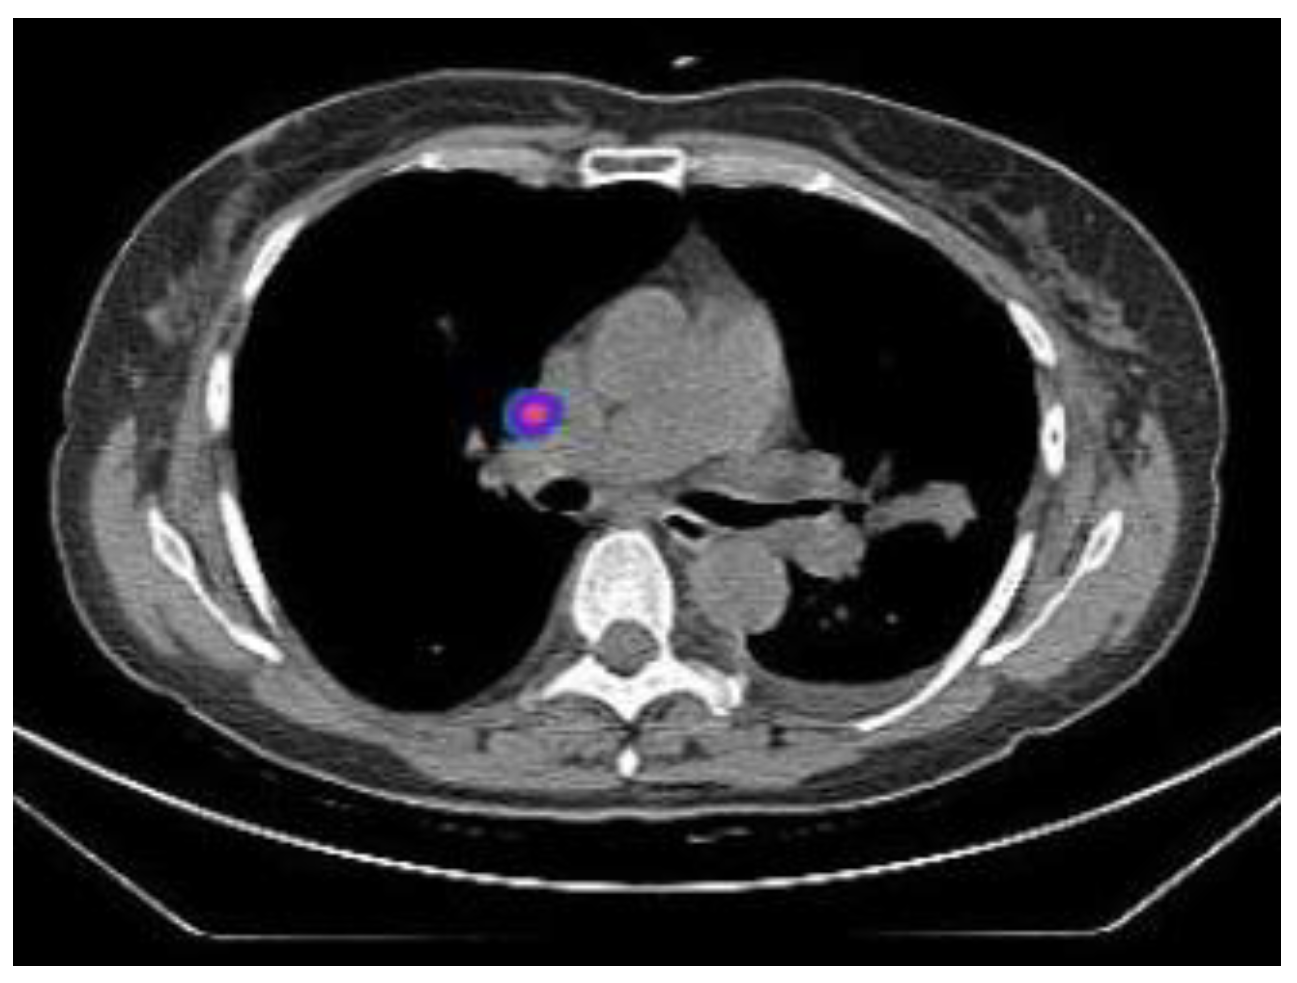

2.2.1. TIME 0: Lesion marking and SPECT Analysis

| Site of Lung Cancer | Histotype | SPECT-Positive SLN Station | Intraoperative Positive SLN Station | |

|---|---|---|---|---|

| Patient 1 | LUL | ADC | 10 | 10 |

| Patient 2 | RLL | ADC | * | 9 |

| Patient 3 | RUL | ADC | 11 | 11 |

| Patient 4 | LLL | ADC | # | 11 |

| Patient 5 | RUL | ADC | # | 4 |

| Patient 6 | RUL | ADC | 10 | 10 |

| Patient 7 | LUL | SCC | * | 5 |

| Patient 8 | RUL | ADC | 10 | 10 |